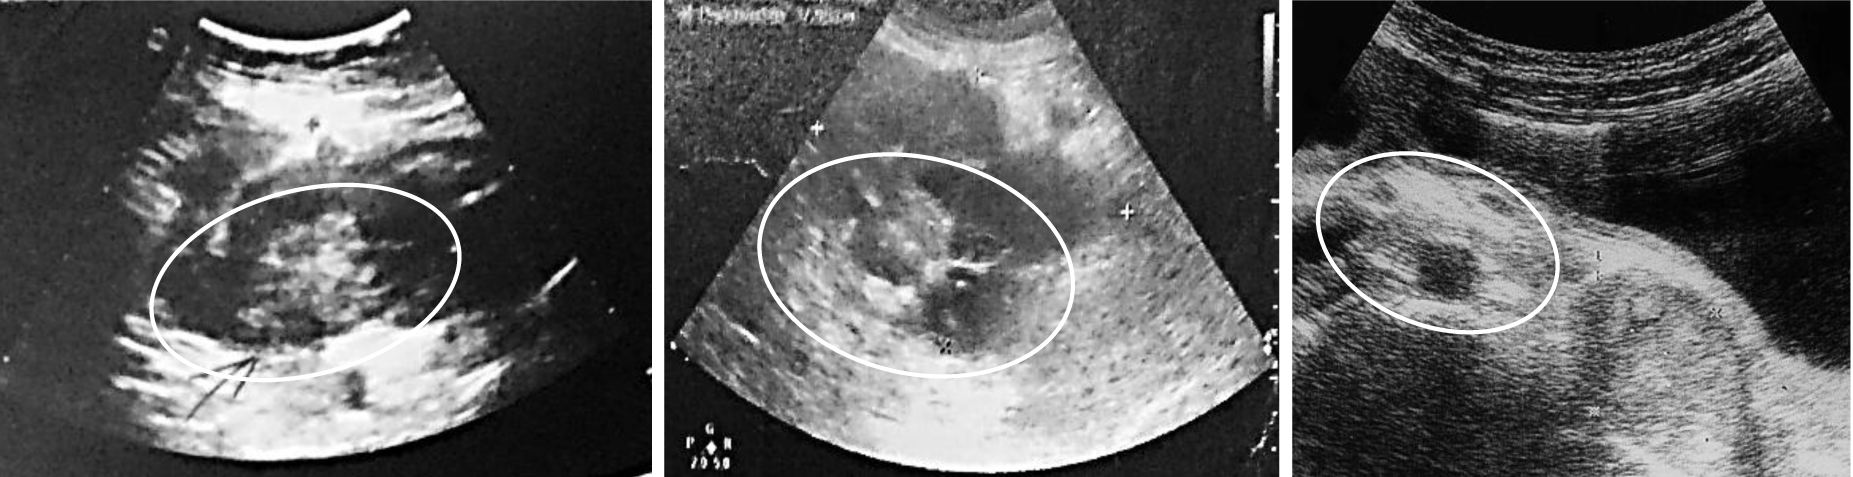

Диагностическая ценность, чувствительность и специфичность методов диагностики ООТК в экстренной ситуации и при плановом обследовании различны [11, 12]. Обзорная рентгенография позволила выявить свободный газ в брюшной полости у 10 из 12 пациентов (83,3 %) с перфорациями тонкой кишки и перитонитом. Еще у двух больных прикрытые перфорации были выявлены во время лапаротомии. Ультразвуковое исследование на фоне кишечной непроходимости (n = 51) позволило выявить ОТК у 20 пациентов (39,2 %), при этом у 17 пациентов (33,3 %) в стенке кишки были визуализированы гипоэхогенные, однородные, преимущественно внутриполостные структуры с ее утолщением и деформацией (рис. 2), признаки инвагинации у 3 (5,9 %) (рис. 3). У 31 пациента ОТК как причина ОКН выявлена не была (60,8 %).

Рис. 2. Гетерогенные внутрипросветные структуры неправильной формы на фоне расширенных петель тонкой кишки (выделены белым контуром)

Рис. 3. Ультразвуковая картина инвагинации, инвагинат отмечен белым контуром